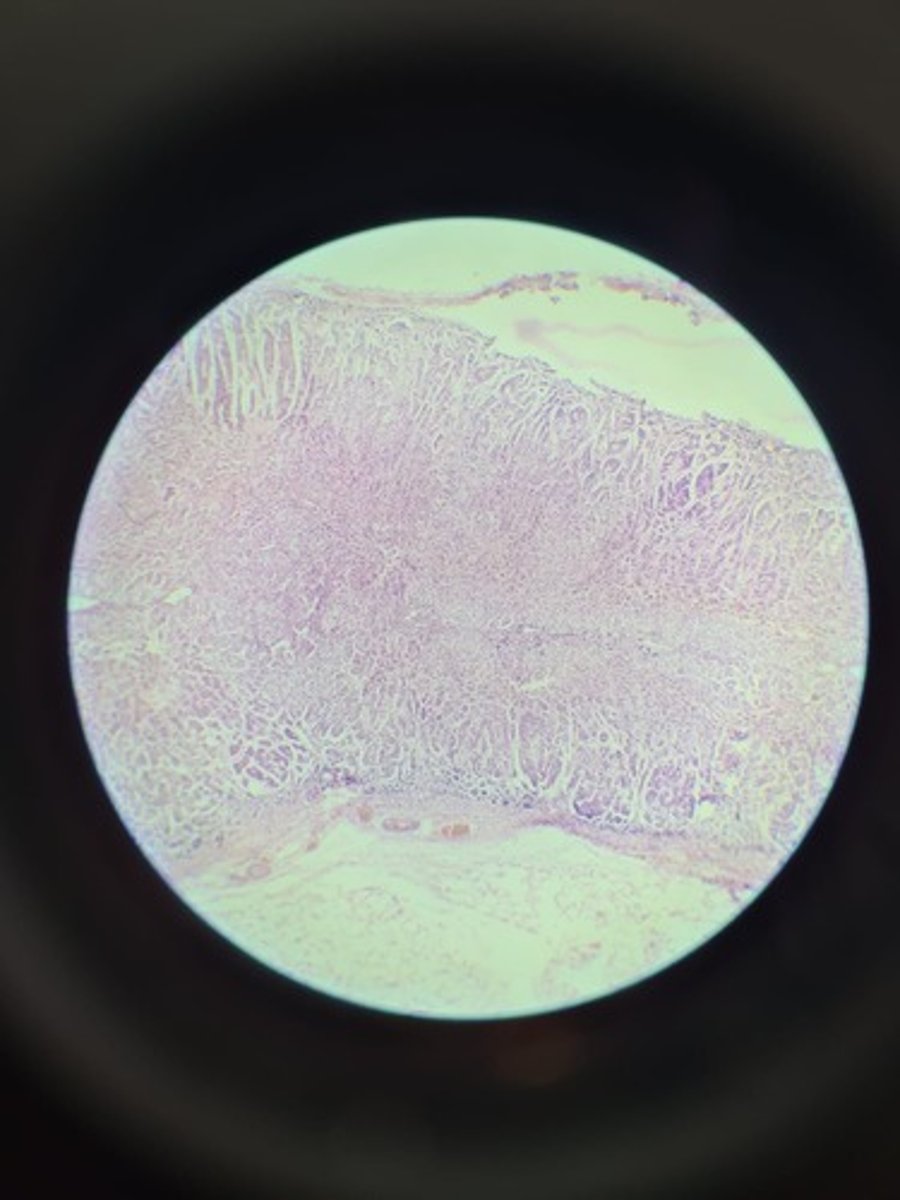

Tonsils HE

Tonsils HE

Tonsils HE